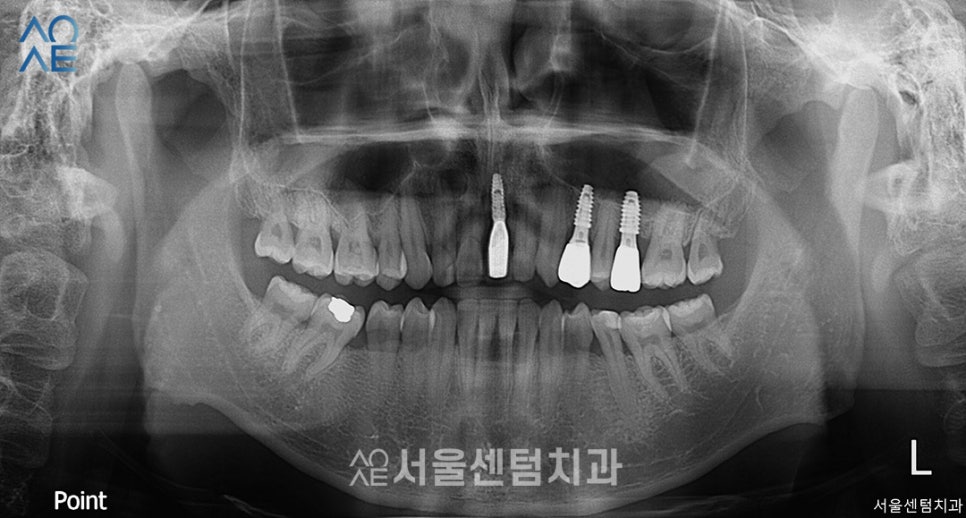

이 분의 경우엔 치아가 이미 상실한 상태라

본인도 임플란트가 필요하다는 점을

인지한 상태로 내원해주셨습니다.

앞니와 어금니를 상실하셨고

잇몸도 전체적으로 많이 내려와있는 상태였죠.

복합적인 치료가 필요하기에

엑스레이 사진과 함께 차근차근 설명해드렸습니다.

(엑스레이에선 왼/오가 반대로 나옵니다)

| (1) 현재 상태🔹 앞니1개, 어금니 3개 상실🔹 전체적으로 잇몸 많이 내려가 있는 상태🔹오른쪽 위에는 식립할 공간 부족 |

| (2) 치료 계획🔹앞니 1개, 어금니 2개 임플란트 식립🔹잇몸치료 & 충치치료 필요🔹왼쪽 위 상악동 거상술 필요 |